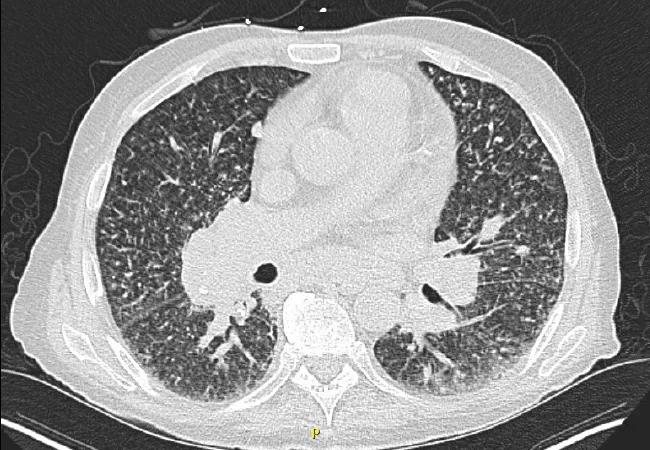

CT of chest

There were several atypical features related to idiopathic pulmonary hypertension. They had periungual erythema and periorbital and forearm violaceous, erythematous and edematous dermatitis. A CT of the chest (Figure 1) revealed hilar/mediastinal lymphadenopathy, multiple bilateral pulmonary nodules, chronic interstitial prominence and interlobular thickening suggestive of pulmonary veno-occlusive disease (PVOD)/pulmonary capillary hemangiomatosis. The initial laboratories demonstrated hypereosinophilia (2700 eosinophils /uL). The team involved consultants from the advanced lung disease service, dermatology, rheumatology and immunology.